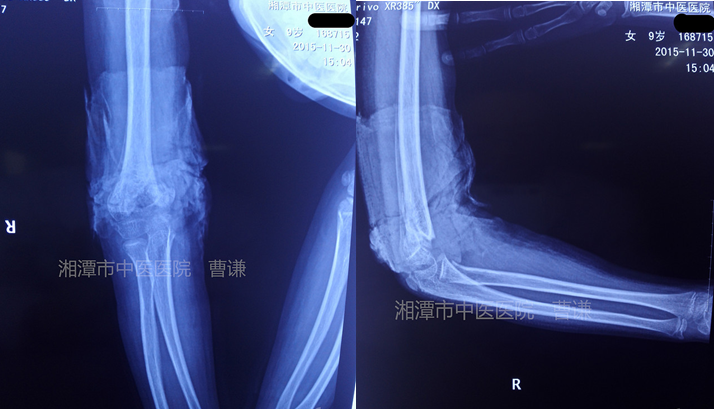

采用楊氏四步復(fù)位法整復(fù)骨折,拍片復(fù)查示斷端前后有移位,考慮可以通過塑形修復(fù),繼續(xù)維持小夾板固定。

治療一月余拍片復(fù)查示骨痂生長明顯,但斷端可見尺傾,鮑曼角堪憂!發(fā)生肘內(nèi)翻可能性大!